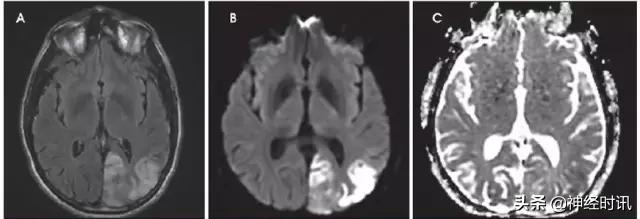

转移性病变

大量细胞转移灶,尤其是小细胞肺癌,可以表现为因致密细胞聚集所致的弥散受限,且可能与急性或亚急性栓塞性卒中相混淆(图24)。前者的一些鉴别特征包括存在周边血管性水肿、周边强化和其它的脑实质外病变(如颅骨病变)。

图24 一位51岁的女性小细胞肺癌患者,因每天早晨突然出现的恶心、呕吐而就诊。其小脑存在多发性弥散受限病灶(A:DWI,B:ADC),并伴有强化(C:T1WI增强扫描)。